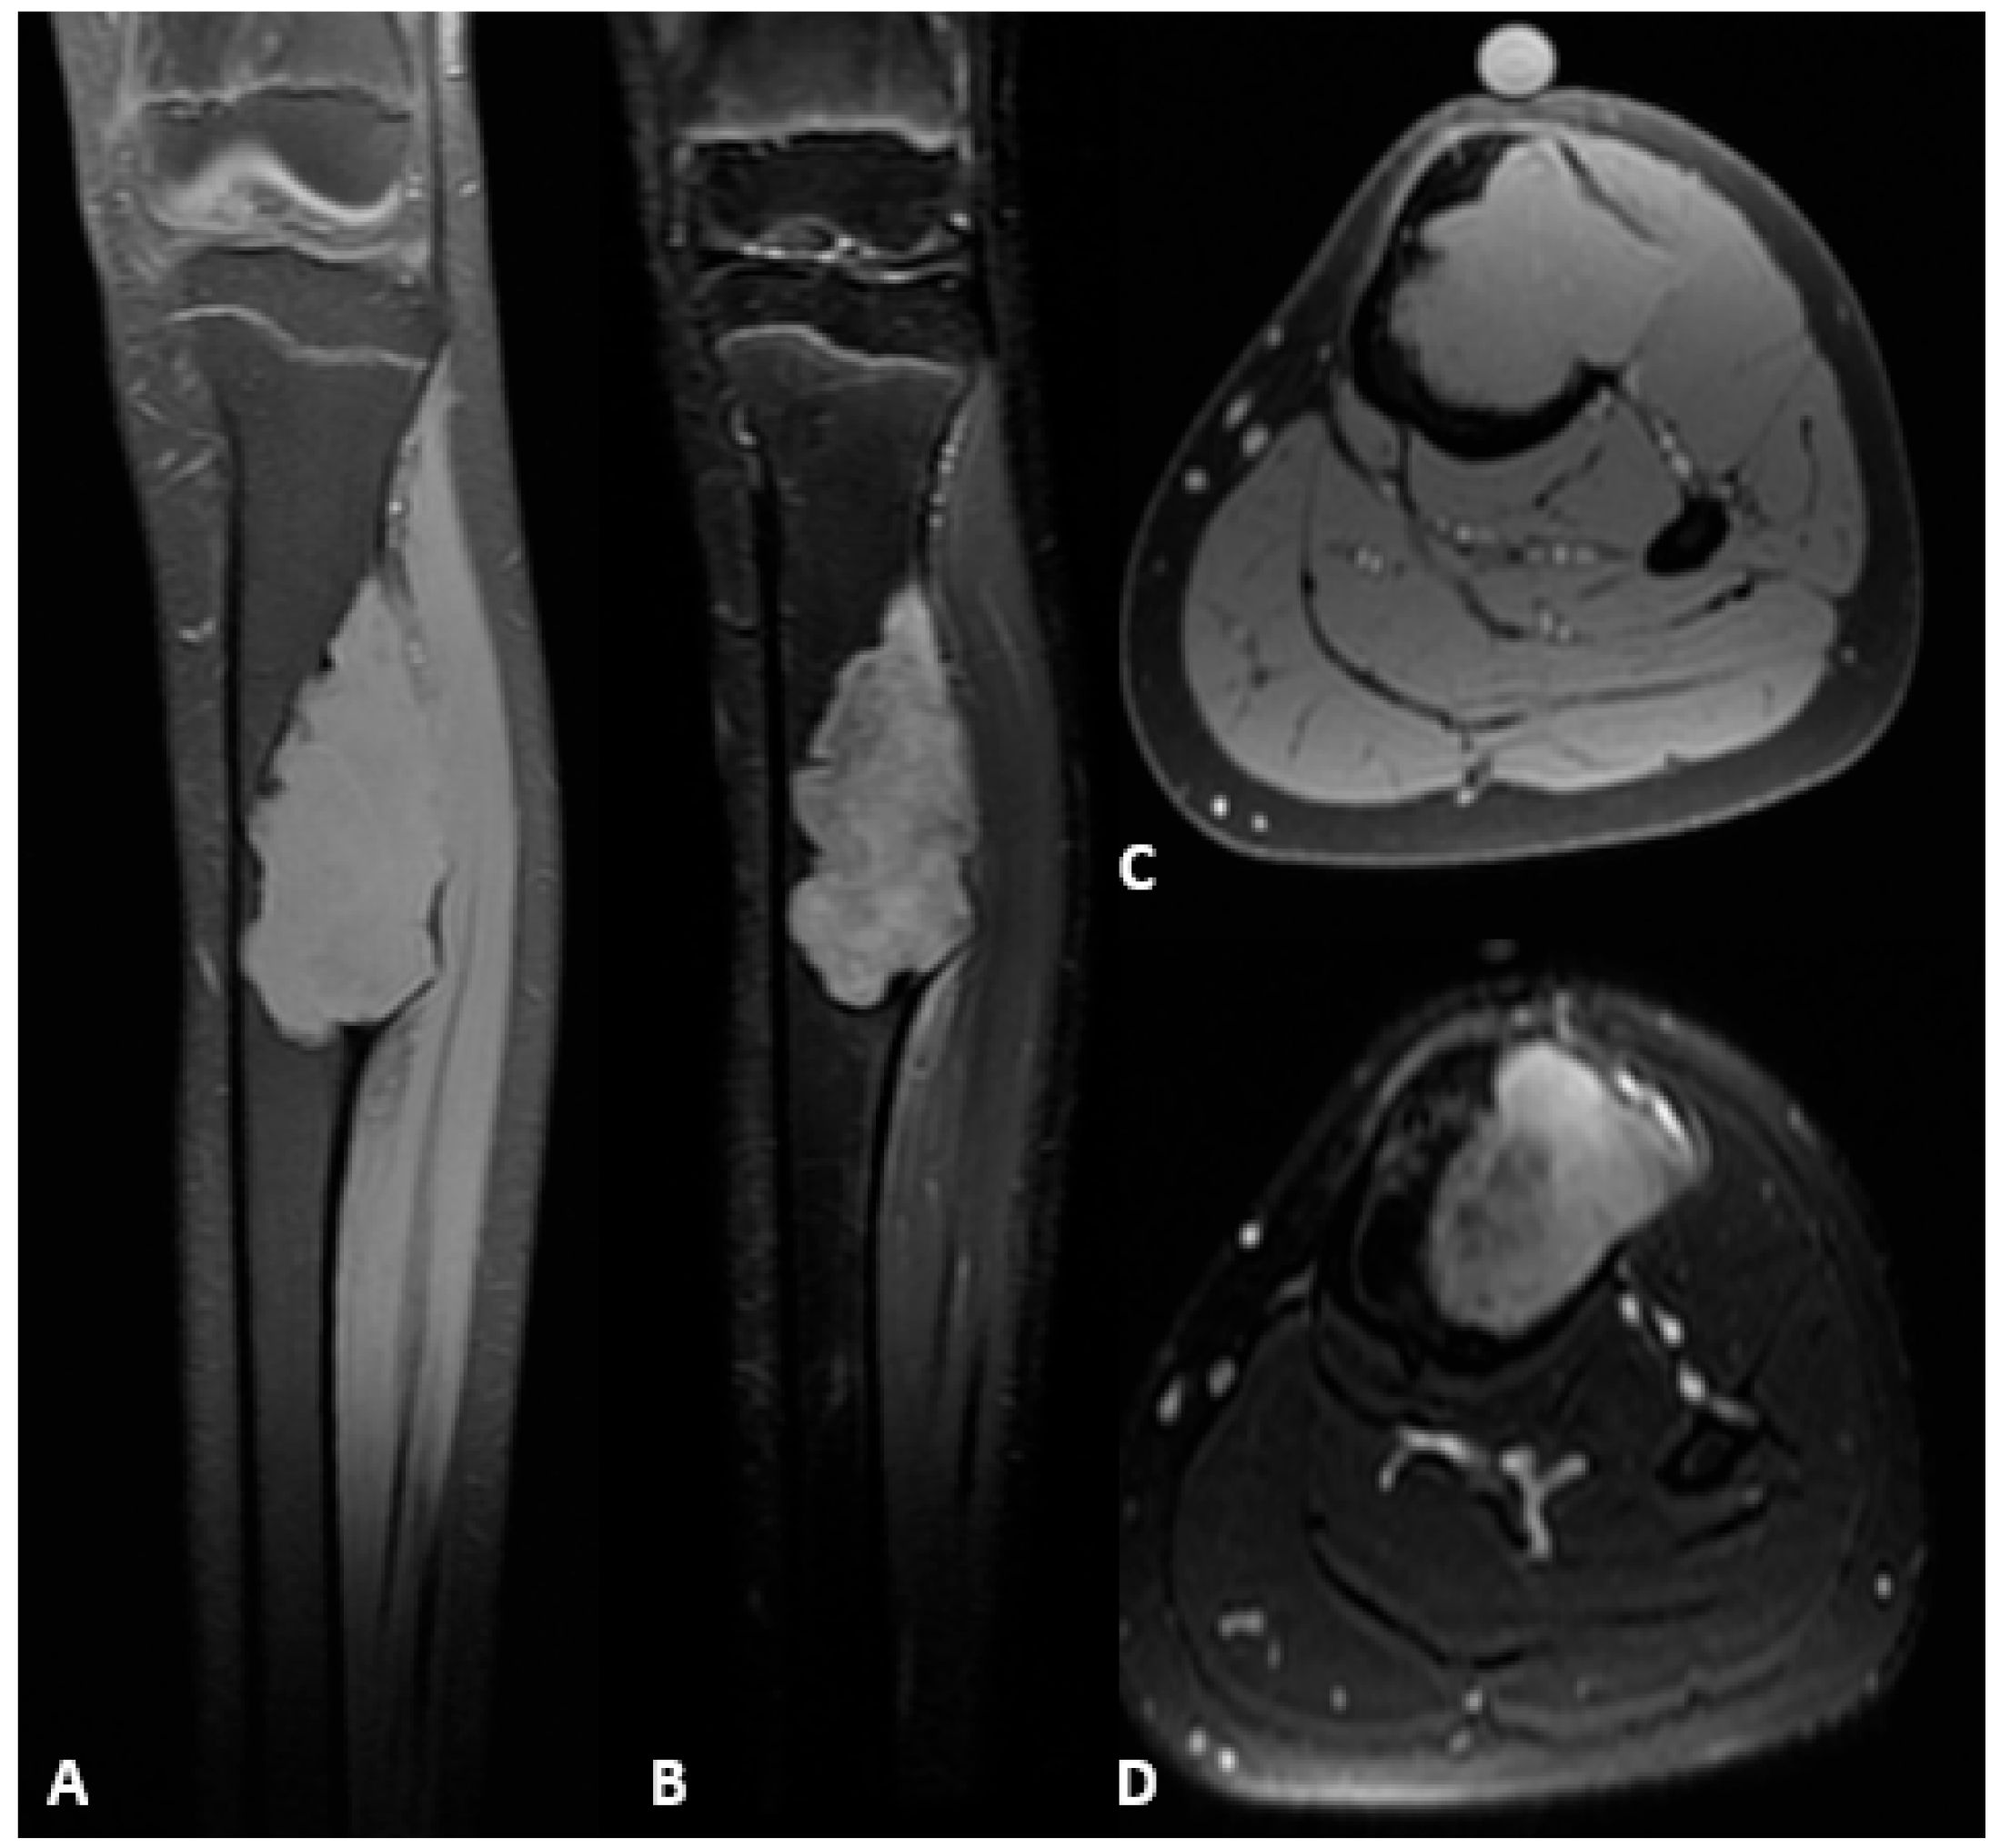

Figure 2.

Preoperative MRI of the left tibial diaphysis demonstrating an OFD/LA. (A) Hypointense lesion on T1-weighted sequence, coronal plane. (B) Hyperintense lesion on T2-weighted fat-suppressed sequence, coronal plane. (C) Hypointense lesion on T1-weighted sequence, axial plane. (D) Hypointense lesion on T2-weighted sequence, axial plane.